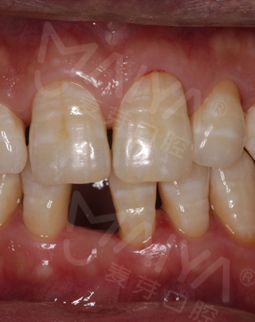

我是个私企老板,今年39岁。前几年由于一些意外,使我的前牙掉了,特别影响形象,很多都问我这年纪轻轻牙咋就掉了......后来做了活动假牙,但是清洁特别不方便,还感觉挺难受的。

经过数字化的拍片检查后发现,我的牙周情况还是蛮不错的,可以用MAC数字化精确种植牙实现8分钟种稳一颗牙,而且工作人员说我可以作为直播案例主角分享自己的故事,感到非常荣幸。